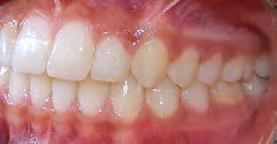

El tiempo de tratamiento fue de 2 años y 9 meses se lograron los objetivos del tratamiento manteniendo el perfil facial, y las relaciones esqueléticas maxilomandibulares. Se realizó la tracción del 13, la corrección de rotaciones dentales en el maxilar, se mantuvo la clase I molar izquierda y se obtuvo la clase I molar derecha. La clase I canina izquierda, y se logró la clase I canina derecha, cerrar mordida abierta de sectores laterales, corrección del overjet y overbite, corrección de líneas medias dentales, manejo de Bolton de arcada superior, mejorar estado periodontal, lograr correcta intercuspidación, guía de desoclusión canina y guía incisiva y la restauración de los dientes 12 y 22

(Figura 5). Una vez terminado el tratamiento, la estabilidad a largo plazo mediante la retención con un circunferencial con finger en los incisivos 12 y 22 para la arcada superior y retenedor termoformado para la arcada inferior.

Radiografía panorámica final el canino 13 es incorporado al arco (Figura 5) y los terceros molares en etapa de formación.

Estudios intraorales finales en las fotografías oclusales, se ven los laterales 12 y 22, así como la incorporación del canino al arco con torque adecuado (Figura 6). En la lateral derecha e izquierda la restauración estética de los laterales superiores,

sin rotaciones ni discrepancia de Bolton.

Figura 5. Radiografía Panorámica. Figura 6. Comparación inicio-final en oclusión.